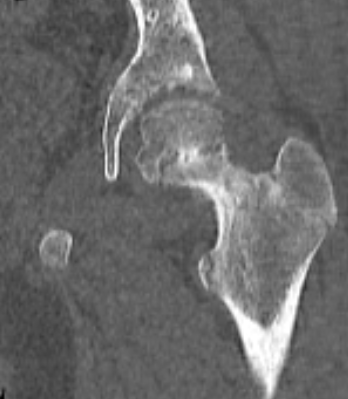

Костный

мостик, прошивающий зону роста головки бедра у мальчика 12 лет с юношеским

эпифизеолизом головки бедра слева.

Фронтальный скан РК – томографии.

Давность заболевания 6 месяцев, за помощью не обращались. На момент

осмотра: небольшая хромота, жидкость в полости левого тазобедренного сустава,

боли при ходьбе.